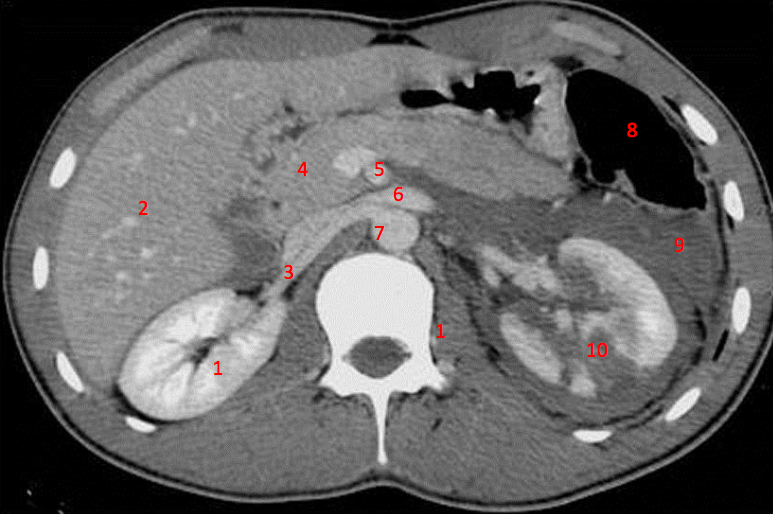

1

Number 3?

IVC

2

Number 1?

13

Number 4?

Head of pancreas

14

Rt diaghragmatic crus

16

Number 2?

21

Number 5?

Rt ureter

22

Number 6?

Descending colon

23

Number 9?

Superior mesenteric artery

25

Number 7?

Abdominal aorta

28

Rt renal artery

31

36

Number 8?

Splenic vein

39

Spleen

42

Rt psoas

46

Lt renal vein

47

Number 10?

Rt kidney

48

Duodendum

52

Traumatic laceration of Lt kidney

53

Lt erectae spinae muscle